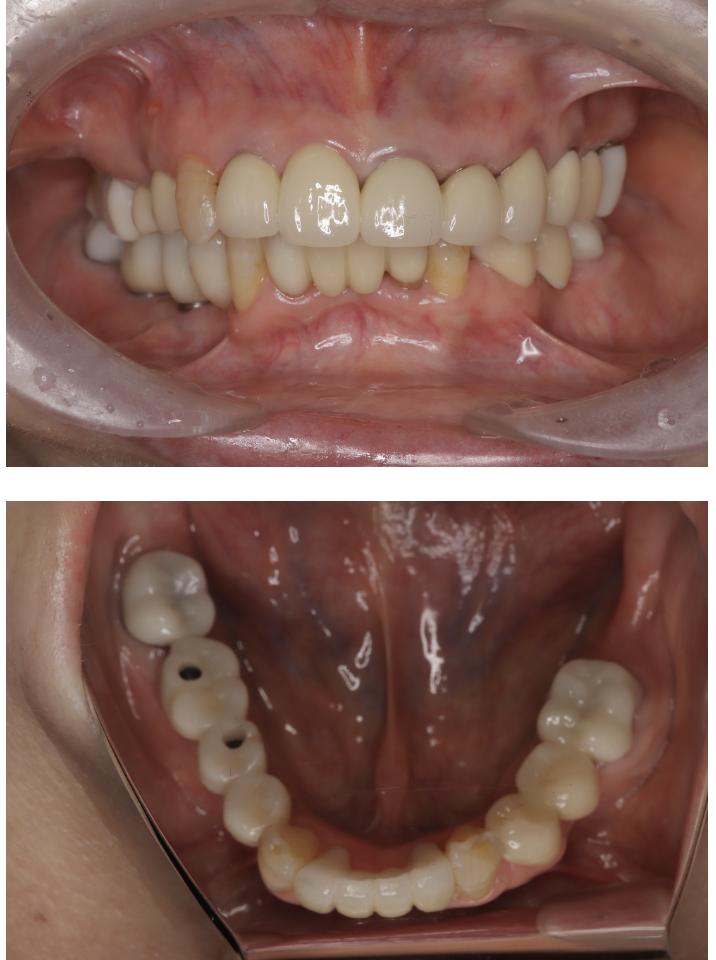

インプラント 16 No.98

Before

After

| 備考 | 院長より 残念ながら保存できなかった歯を抜歯して、インプラントを埋入しました。3本失ってしまったのですが、2本埋入れてブリッジタイプで対応しています。インプラント(人工歯根)と被せ(フルジルコニアCr)はネジで連結してあり必要に応じて外してチェックできるようになっています。写真ではメンテナンス時でネジ穴が見える状態になっています。通常はネジ穴はプラスティックで蓋をして見えない状態になっています。 |